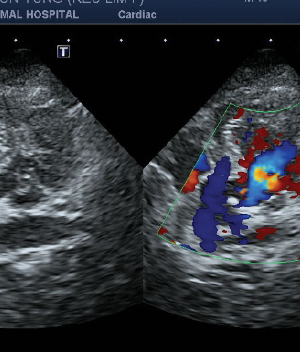

• 심장 초음파

• 노령묘 이거나 흉부 x-ray에서 심장질환이 의심되는 경우 심장 초음파를 진행하고 있습니다.

• 실제로 고양이는 특별한 증상이 없더라도 비대성 심근증(HCM)이 많이 발견되는 편입니다. 고양이의 심장질환은 심장 초음파에서 정확한 진단이 가능합니다.